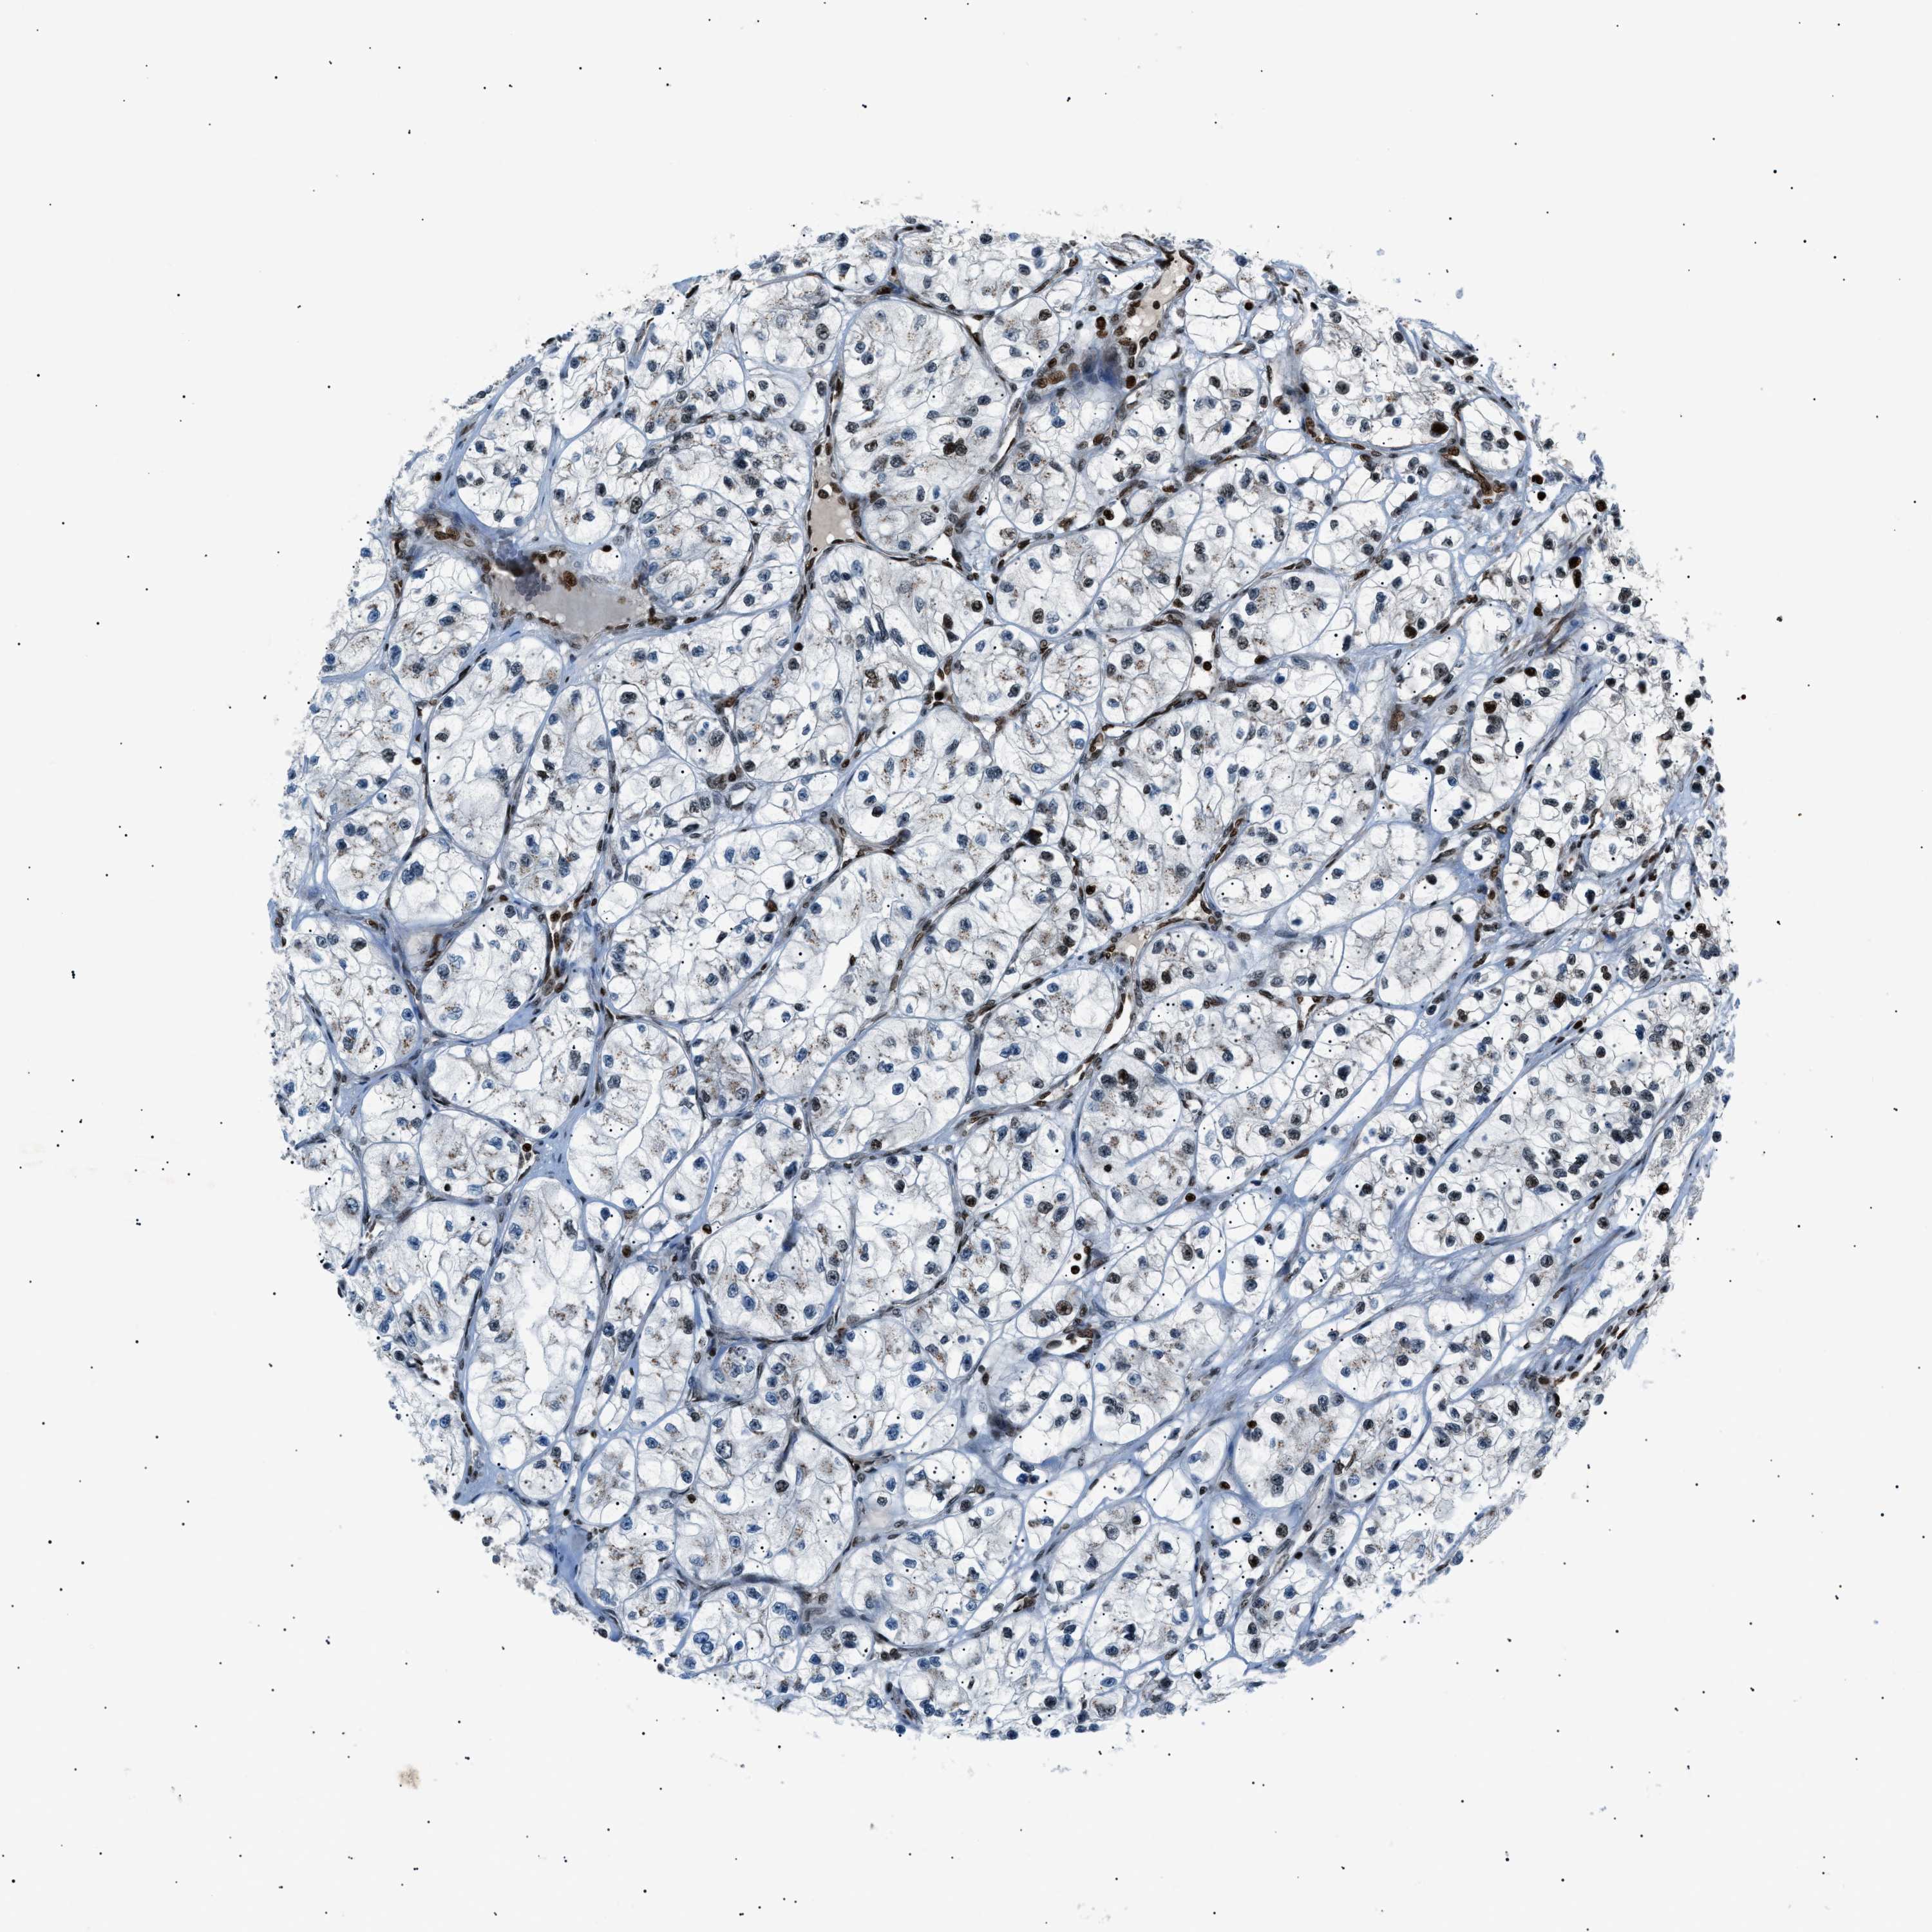

KIDNEY RENAL CLEAR CELL CARCINOMA (VALIDATION) - Interactive survival scatter ploti

The Survival Scatter plot shows the clinical status (i.e. dead or alive) for all individuals in the patient cohort, based on the same data that underlies the corresponding Kaplan-Meier plots. Patients that are alive at last time for follow-up are shown in blue and patients who have died during the study are shown in red.

The x-axis shows the expression levels (FPKM) of the investigated gene in the tumor tissue at the time of diagnosis. The y-axis shows the follow-up time after diagnosis (years). Both axes are complimented with kernel density curves demonstrating the data density over the axes. The top density plot shows the expression levels (FPKM) distribution among dead (red) and alive patients (blue). The right density plot shows the data density of the survived years of dead patients with high and low expression levels respectively, stratified using the cutoff indicated by the vertical dashed line through the Survival Scatter plot. This cutoff is automatically defined based on the FPKM cutoff that minimizes the p-score. The cutoff can be changed by dragging the vertical line or by entering a cutoff value in the square labeled "Current cut-off".

Under the Survival Scatter plot the p-score landscape (black curve; left axis) is shown together with dead median separation (red curve; right axis). Dead median separation is the difference in median mRNA expression between patients who have died with high and low expression, respectively. It is calculated as follows: median FPKM expression of dead patients with high expression - median FPKM expression of dead patients with low expression. This is intended to aid the user in visually exploring custom cutoffs and the associated p-scores and dead median separation.

Individual patient data is displayed and can be filtered by clicking on one or more of the category buttons on the top of the page. Categories describing expression level and patient information include: high, low, alive, dead, female, male and tumor stages. The scale of the x-axis can be toggled between linear and log-scale by clicking on the "x log" button. Mouse-over function shows TCGA ID, patient information and mRNA expression (FPKM) for each patient.

& Survival analysisi

Kaplan-Meier plots summarize results from analysis of correlation between mRNA expression level and patient survival. Patients were divided based on level of expression into one of the two groups "low" (under cut off) or "high" (over cut off). X-axis shows time for survival (years) and y-axis shows the probability of survival, where 1.0 corresponds to 100 percent.

PRKX is not prognostic in Kidney Renal Clear Cell Carcinoma (validation)

Best expression cut offi

Based on the FPKM value of each gene, patients were classified into two groups and association between prognosis (survival) and gene expression (FPKM) was examined. The best expression cut-off refers the FPKM value that yields maximal difference with regard to survival between the two groups at the lowest log-rank P-value. Best expression cut-off was selected based on survival analysis .

When clicking on this number, the vertical dashed line indicating cut-off, the interactive survival plot, and the Kaplan-Meier curve will be adjusted to show results based on the best expression cut-off.

: 8.82

TCGA RNA samplesi

RNA-seq data is reported as average FPKM (number Fragments Per Kilobase of exon per Million reads), generated by the The Cancer Genome Atlas (TCGA) .

Normal distribution across the dataset is visualized with box plots, shown as median and 25th and 75th percentiles. Points are displayed as outliers if they are above or below 1.5 times the interquartile range. FPKM values of the individual samples are presented next to the box plot.

Average pTPM 11.5

Number of samples 100